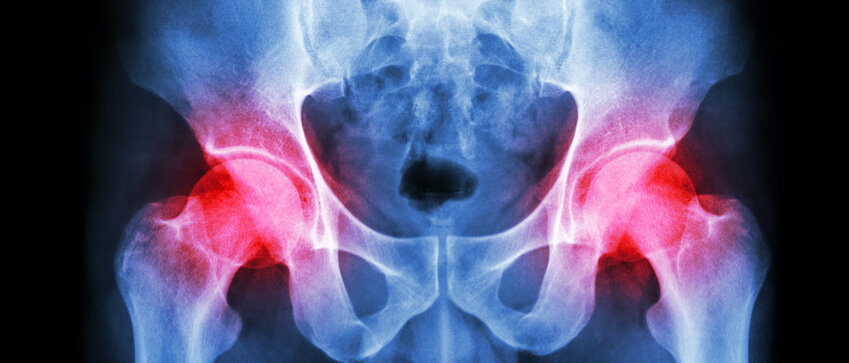

Hüftimplantate | Operation

METALLABRIEB SCHÄDIGT KNOCHENBILDENDE ZELLEN

Implantate, bei denen sowohl Kugelkopf als auch Gelenkpfanne aus Cobalt-Chrom-Molybdän-Legierungen bestehen, können im menschlichen Körper unter Belastung Metallionen freisetzen.